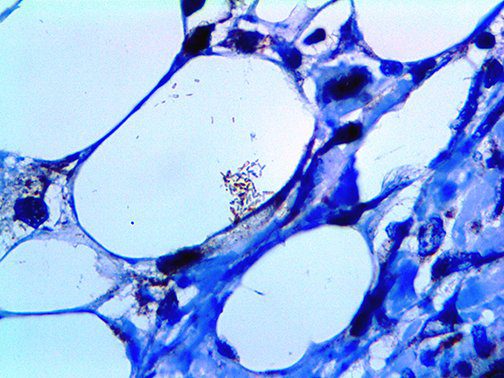

Clinical and laboratory manifestations of HLH include fever, enlarged liver and/or spleen, neurologic dysfunction, coagulopathy, liver dysfunction, cytopenias (i.e., low levels of erythrocytes, leukocytes, and/or platelets), hypertriglyceridemia, hyperferritinemia, hemophagocytosis, and eventually diminished NK cell activity as the immune system becomes progressively paralyzed. HLH can be familial (primary HLH) or secondary to another disease process (sHLH), such as rheumatic disease, in which it is referred to as macrophage activation syndrome (MAS, characterized by elevated ferritin).

This activation induces inflammatory monocytes to highly express IL-6, starting a localized and then systemic cascade effect that results in hyperproduction of IL-6, which accelerates the inflammatory process. Because IL-6 also increases vascular permeability, excessive levels cause blood vessels to become very leaky. This, along with clotting factors released from vascular endothelial cells, stimulates the coagulation cascade, resulting in microthrombosis (tiny clots), which leads to ischemia and tissue death of the kidney, intestines, heart, liver, brain and extremities.